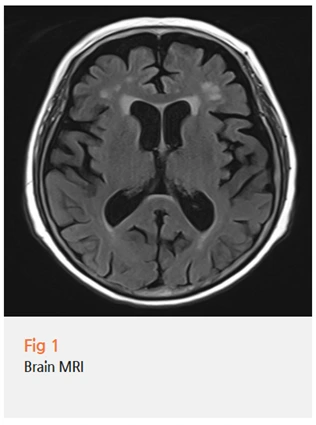

무엇보다 뇌 영상 검사가 필요하다고 판단하여

당일 뇌 MRI와 MRA 검사를 시행했습니다.

다행히 급성 뇌경색이나 뇌출혈 같은

응급 상황을 시사하는 소견은 없었어요.

하지만 영상을 자세히 보니, 환자분의 연령을 고려했을 때

예상보다 진행된 뇌위축 소견이 관찰되었습니다.

특히 기억을 담당하는 해마 영역의 위축이 두드러졌고,

이는 알츠하이머형 치매의 초기 단계에서 흔히 보이는 소견이에요.

뇌혈관 상태는 비교적 양호했지만,

전반적인 뇌 용적 감소가 확인되었습니다.

MMSE 점수와 영상 소견, 그리고 임상 증상을 종합했을 때

이 환자분은 초기 치매로 진단할 수 있었습니다.